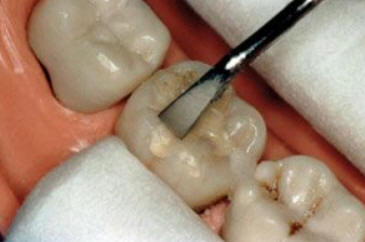

Código 3 (Caries moderada) in vitro. Los códigos 3 in vivo debe ser sellado para evitar el avance del proceso carioso. (MNO)

Código 4 (Caries moderada) in vitro. Los códigos 4 in vivo deben ser tratados en forma operatoria con preservación dental (MOPD), porque presentan dentina infectada.